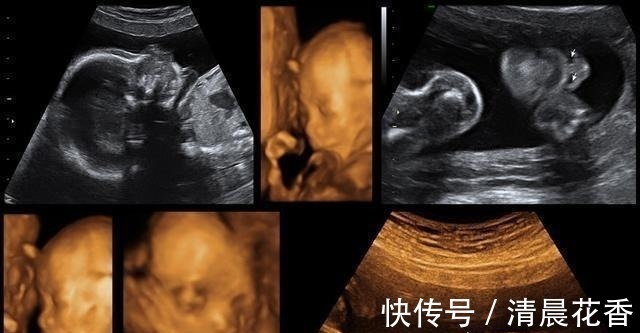

四维|做四维时宝宝趴着不愿意动,原来是这些原因,做好这点一次通过

在怀孕之后那么四维大排畸检查是整个孕期非常重要的一个检查项目,在怀孕20周到18周的时候,除了能够筛查一些比较显著的畸形外,还能够看到宝宝人生中第1张照片,但我在做四维的时候妈妈是很激动的,有的妈妈在做四维的时候一次就成功了,那么有的宝宝可能就会不配合,就做了好几遍。

为什么宝宝做四维的时候不愿意动呢?宝宝处于睡眠时间,其实宝宝的生物钟和大人也会处于一个不同的状态,如果是在做四维的时候,宝宝正在睡觉的时间,那么也就会不愿意动了。宝宝性格比较安静,其实我有一个闺蜜的宝宝在整个孕期也是不爱动的,然后胎动也不多,他就非常的害怕,就及时的去做了,产检也是很正常的,可能是胎动比较轻微,自己也并不是非常的敏感,所以说你就会感觉不到。宝宝比较害羞,毕竟这一次是和爸爸妈妈的,第1次见面,宝宝也就没有做好准备,可能就会比较害羞一些,那么宝宝也就会拿着小手遮住小脸,这样的话医生也就没有办法看清变不了,所以说是需要宝宝动一动才能够看清全貌的。